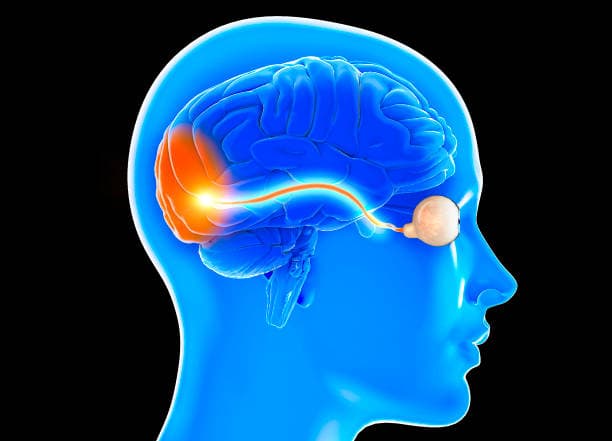

Neuro-ophthalmology is a specialized branch of medicine that bridges the gap between neurology and ophthalmology, focusing on the complex relationship between the nervous system and vision. This field deals with the diagnosis and treatment of visual problems that are related to neurological disorders, encompassing a wide range of conditions that affect the optic nerve, eye movements, and visual processing pathways in the brain.

Neuro-ophthalmology is a specialized field of medicine that intersects the disciplines of neurology and ophthalmology, focusing on the intricate relationship between the nervous system and vision. This unique branch deals with the diagnosis and management of visual disorders that are related to neurological conditions, encompassing a wide range of ailments affecting the optic nerve, eye movements, and the visual processing pathways in the brain. Neuro-ophthalmologists are highly trained specialists equipped to handle complex cases where traditional ophthalmological treatments may not suffice. They address conditions such as optic neuropathies, which include diseases like optic neuritis and ischemic optic neuropathy that involve damage to the optic nerve, resulting in vision loss.

Neuro-ophthalmology is a specialized field of medicine that addresses the intricate relationship between the nervous system and vision. It encompasses the diagnosis and management of a wide range of conditions that affect the optic nerve, eye movements, and visual processing pathways in the brain.